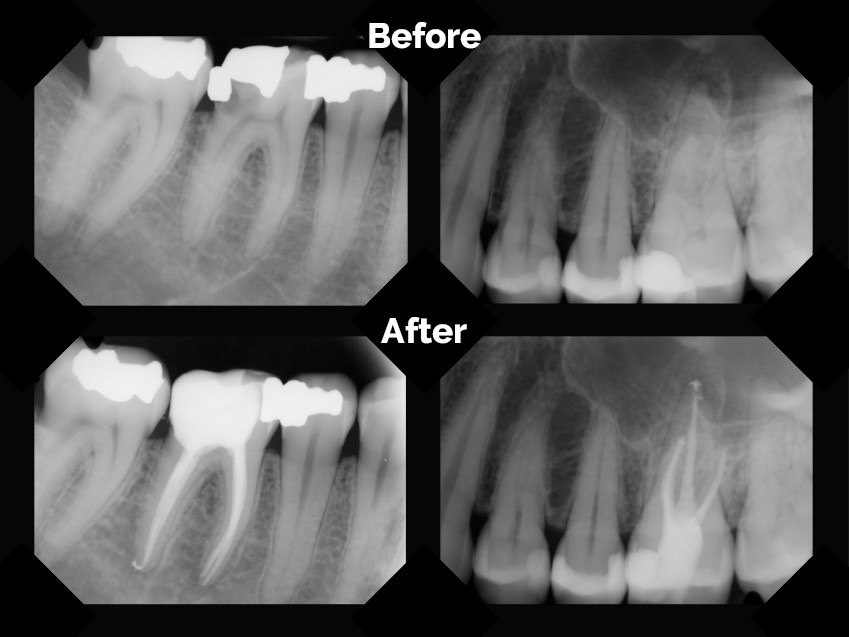

• Зъболекарят прави обстоен преглед, включително рентгенова снимка, за да определи степента на увреждане и броя на кореновите канали.

• Определя се точната дължина на кореновите канали, често с помощта на апекслокатор и контролни рентгенови снимки.

• След като каналите са напълно почистени и дезинфекцирани, те се запълват с биосъвместим материал, най-често гутаперча, която се поставя с помощта на специален сийлър. Целта е да се запечатат херметично каналите, за да се предотврати повторна инфекция.

• Следене: Важни са контролните рентгенови снимки, за да се проследи оздравителният процес в костта.

Преди и След